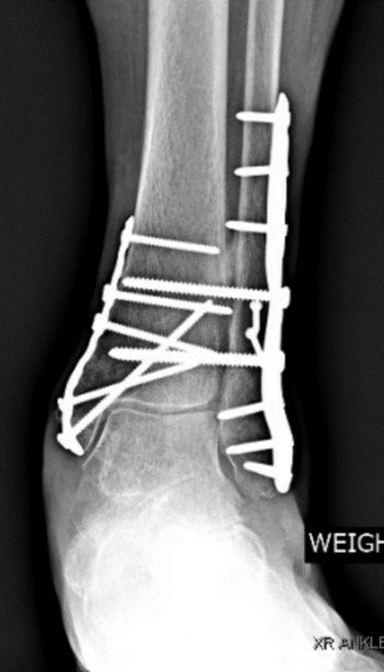

Ankle Fracture-3 Ankle Fracture-2With non-surgical treatment, the ankle bone is realigned, and a plaster splint is placed around the joint, for at least 2-3 weeks. With surgical treatment, the fractured bone is usually accessed by making an incision over the ankle and then the broken pieces are aligned and compressed together. The bones are fixated with screws and usually, a metal plate is then placed on top for added protection and support. The incision is then sutured closed, and the ankle is immobilized with a splint.

After ankle surgery, patients are instructed to avoid placing weight on the ankle by using crutches, a walker, and/or a knee scooter for at least six weeks.